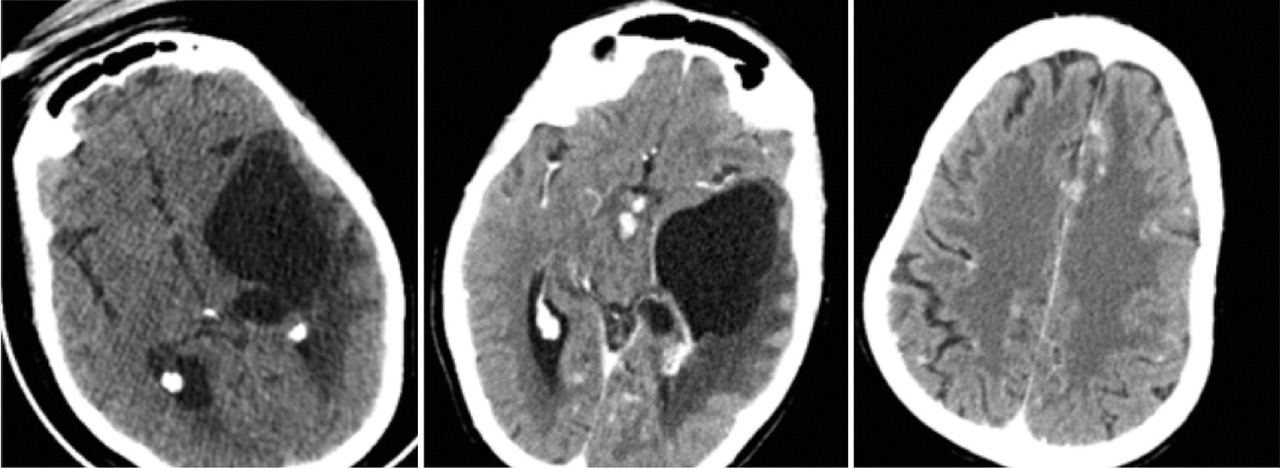

Cette femme de 44 ans avait un tableau d’hypertension intracrânienne et des troubles du comportement, un syndrome pyramidal droit, une paralysie faciale centrale droite, un syndrome confusionnel et un œdème papillaire ; pas de particularité pour le reste de l’examen, notamment pulmonaire. Le bilan biologique (test de sensibilité à la tuberculine, antigène carcinoembyonnaire, métabolisme calcique, cytologie du lavage bronchoalvéolaire) et la radiographie pulmonaire étaient normaux. La tomodensitométrie (TDM) cérébrale (fig. 1 ) montrait une lésion kystique temporale gauche exerçant un effet de masse sur la ligne médiane avec un œdème périlésionnel. Après injection il y avait une prise de contraste micronodulaire leptomeningée diffuse et de la corne occipitale du ventricule latéral gauche. L’imagerie par résonance magnétique (IRM) [fig. 2 ] montrait une volumineuse lésion kystique expansive temporale gauche, dont les parois ne se rehaussaient pas après injection du produit de contraste avec un hypersignal T2 périlésionnel ainsi qu’un engagement temporal. La résection chrirugicale et la corticothérapie permettaient une amélioration neurologique immédiate. L’histologie était en faveur d’un granulome épithéloide gigantocellulaire sans nécrose caséeuse.